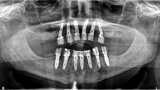

Fig. 20: Post-op panoramic view.